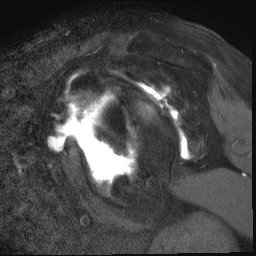

MRI

Rotator cuff tears

MRI with massive supraspinatus tear, subscapularis tear, and large Hill Sachs lesion